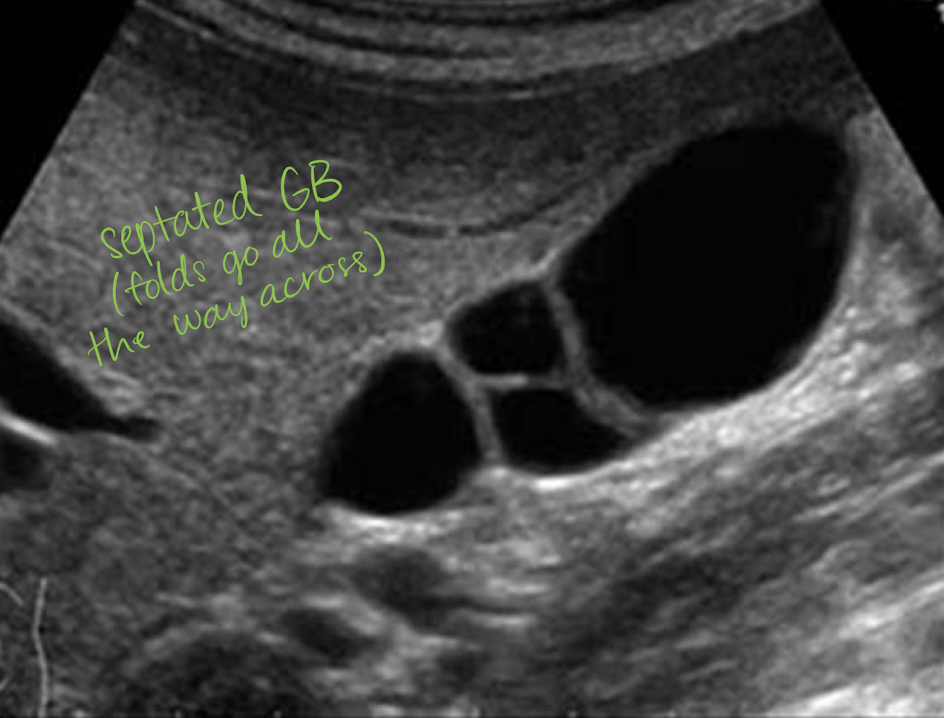

septations

internal division(s) of GB—hyperechoic line

goes all the way across

if not then it is likely a fold

associated with cholelithiasis